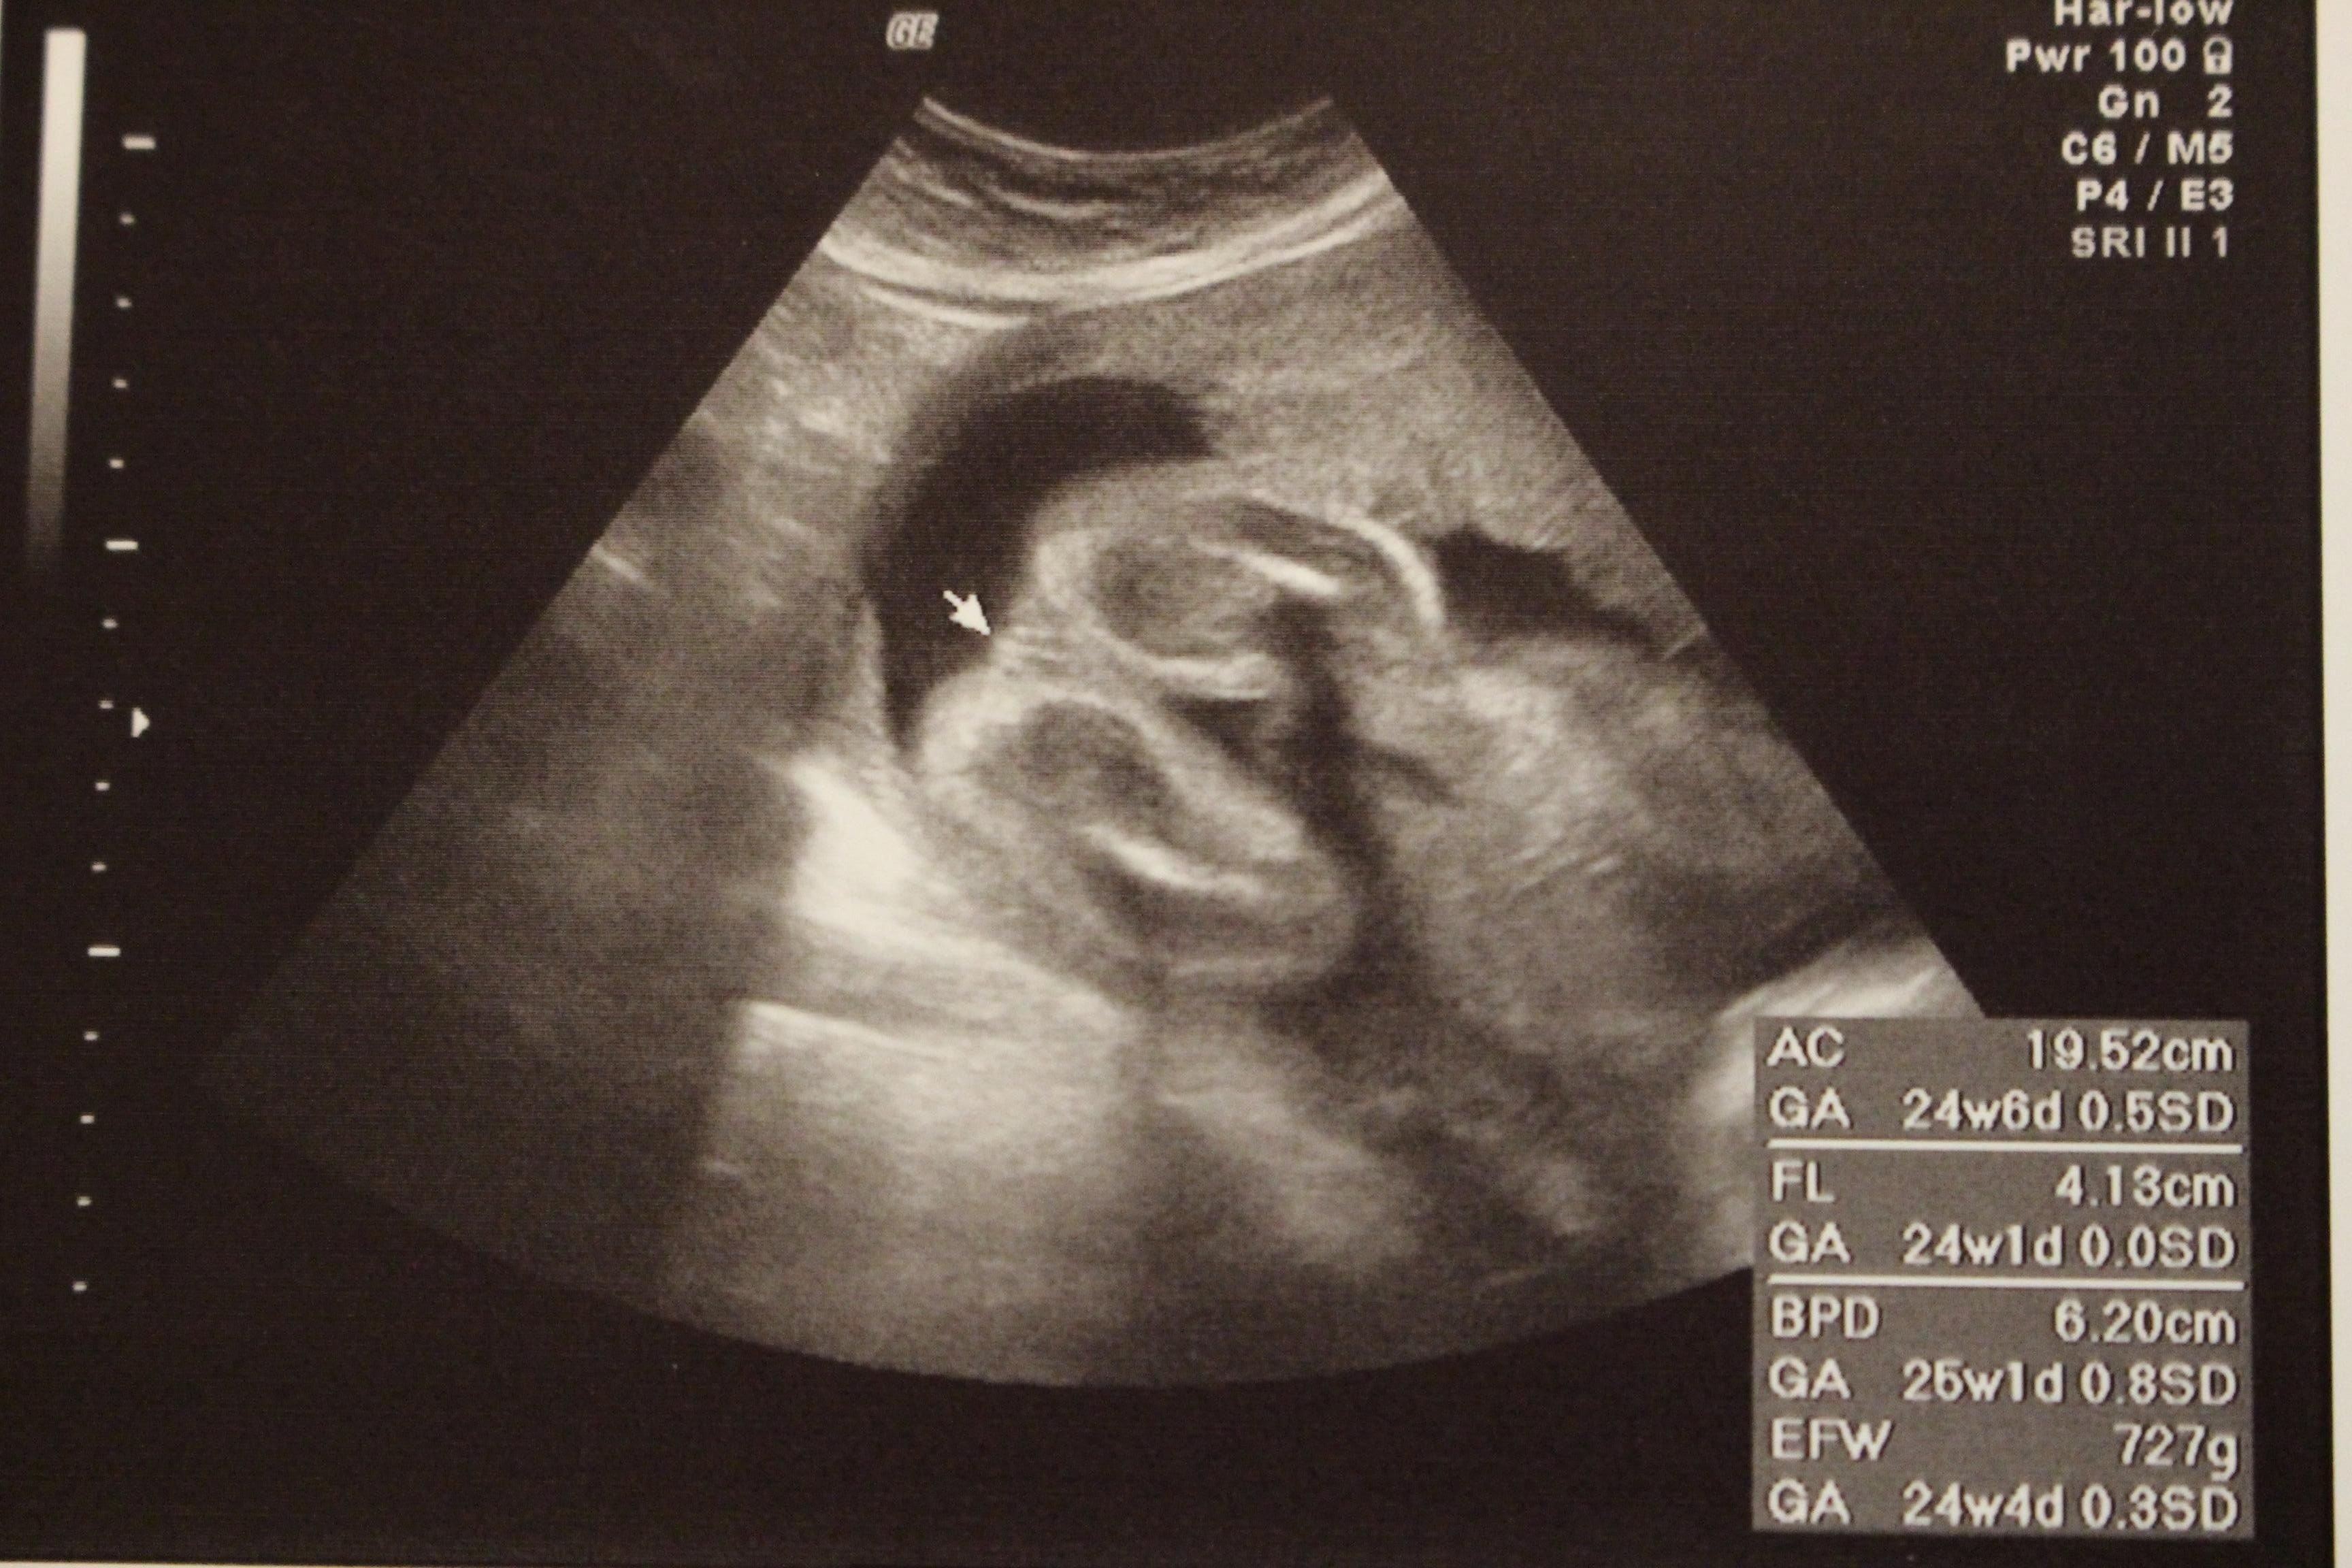

妊娠24週目のエコー写真

2D画像。医師から「今、性別を知りたいですか?それとも楽しみに取っておきますか?」と尋ねられ、名付けや準備に必要だからと教えてもらいました。前夜にみた夢のお告げ通りだったので、ますます神秘的な気持ちになりました。

妊娠24週目4Dの一部画像。手で顔を隠すしぐさと、首にへその緒を巻いている様子が見えます。赤ちゃんの体重727g母体の体重60kg!つわりもおさまった頃で体重管理を意識し始めた時期です。この頃、母親学級で知り合った同じ産院で分娩予定のプレママが管理入院することになり、健診の帰りにお見舞いに行きました。